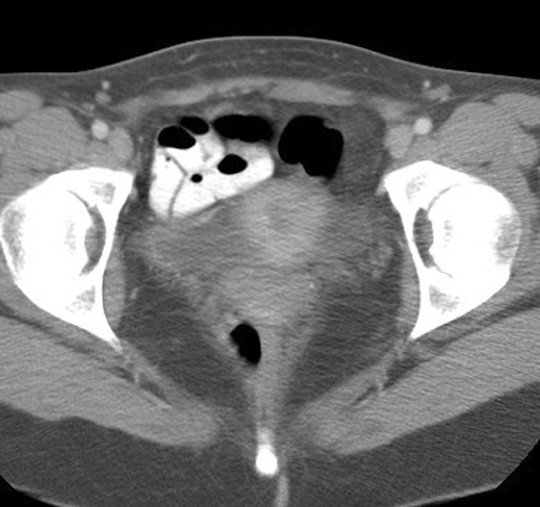

Identify the levator ani. Click the image for labeling.